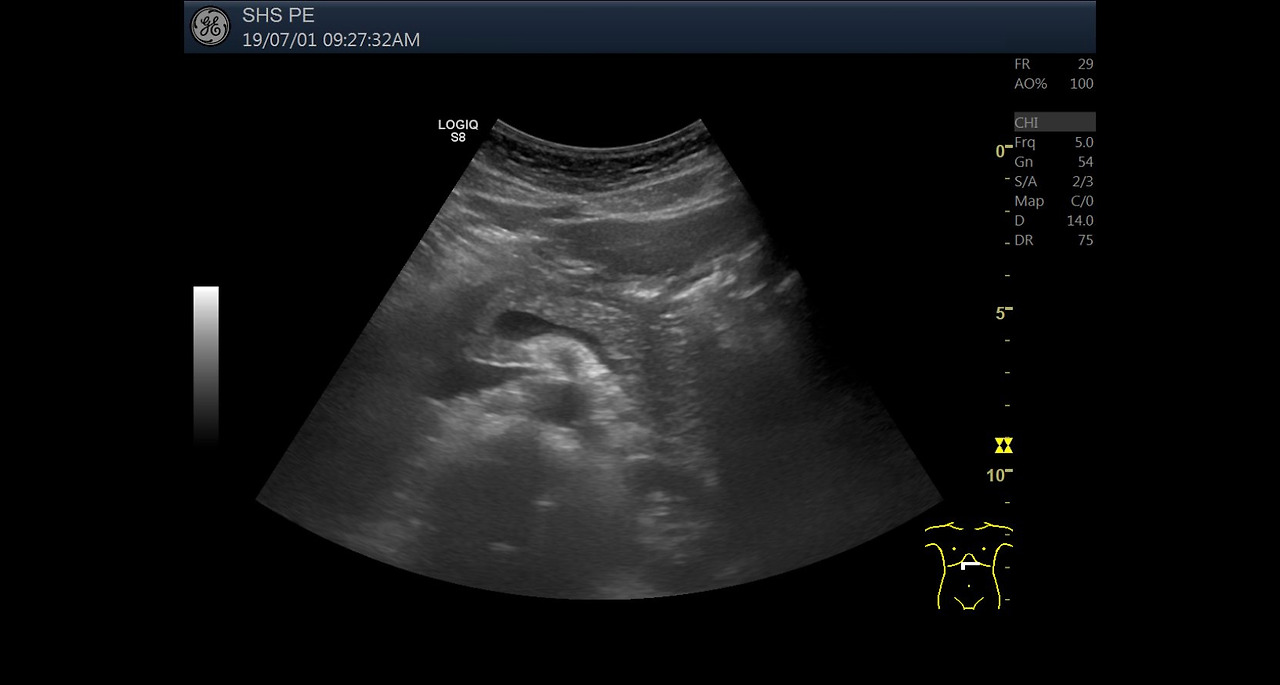

복부 초음파는 초음파(ultrasound)를 이용해 복부 내 장기들의 상태를 확인하는 비침습적 검사 방법입니다. 방사선을 사용하지 않아 인체에 해롭지 않고, 고통 없이 실시간으로 복부 장기들을 관찰할 수 있다는 점에서 가장 기본적이면서도 효과적인 진단도구로 평가받습니다.

초음파 탐촉자(Probe)에서 발생한 고주파 음파가 인체 내부 장기에 부딪혀 반사되며, 복부 초음파로 알 수 있는 것은 바로 이 반사파를 영상화해 간, 담낭, 췌장, 비장, 신장(콩팥), 방광, 대동맥, 림프절 등의 상태를 분석하게 됩니다.